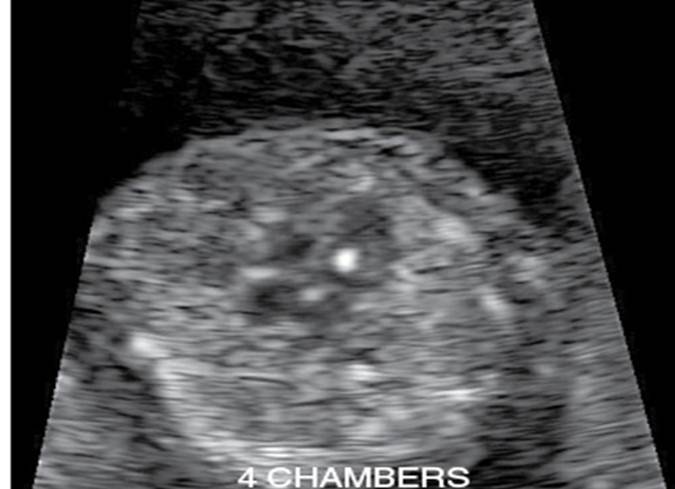

Intracardiac focus